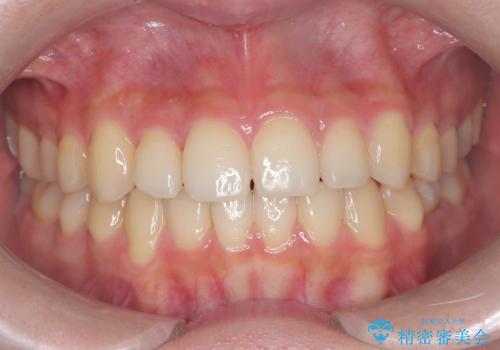

- 患者様は、下顎両側の第1大臼歯(6番)と右上6番の欠損を主訴に来院されました。

通常であればインプラントによる補綴が第一選択となる症例でしたが、患者様ご自身がインプラントを希望されなかったため、矯正治療によって欠損部の閉鎖を図る方針としました。

同時に、親知らず(智歯)の萌出や位置も考慮し、咬合全体のバランスを改善する矯正治療計画を立案しました。

ワイヤー矯正を用いて、欠損部の閉鎖を目的とした後方からの歯の挺出・移動を行いました。

特に、親知らずを活用し、奥歯の噛み合わせを構築することに重点を置きました。

最終的には予定通りインプラントを使用せずに欠損部を閉鎖し、咬合も安定させることができました。